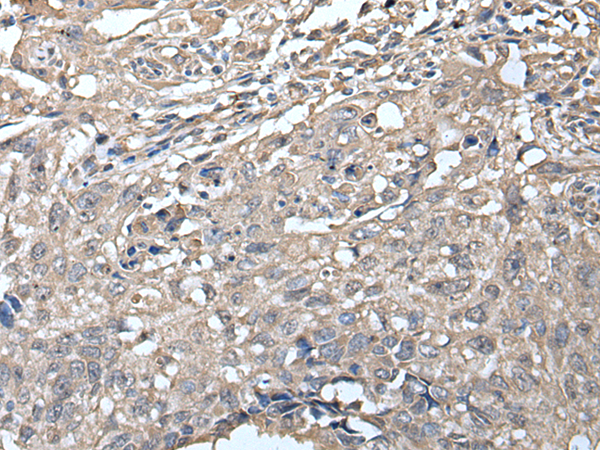

分类: 科研抗体货号: P12879别名: RECQ3; RECQL2; RECQL3应用: IHC反应种属: Human